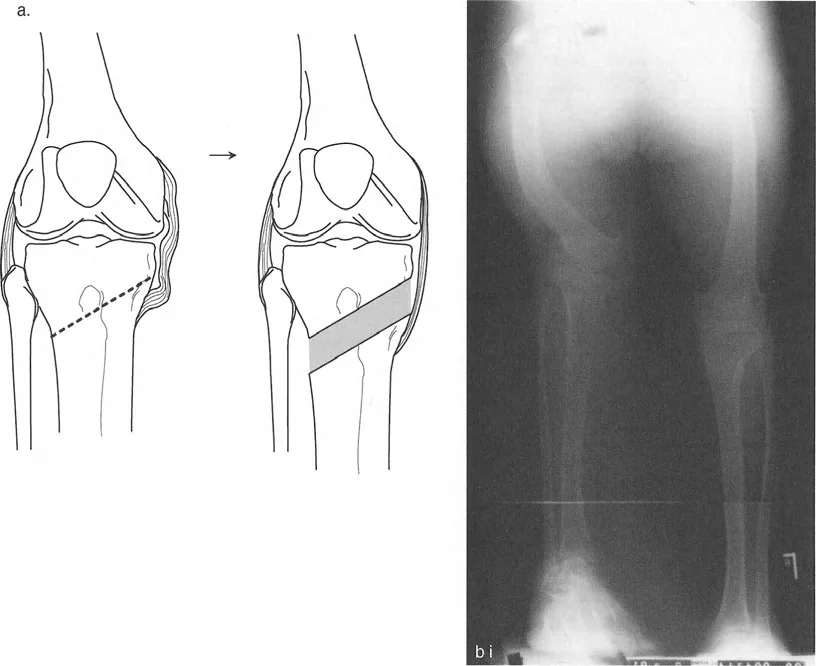

Center of Rotation of Angulation CORA

The Center of Rotation of Angulation is the cornerstone of Paley's preoperative planning method. The CORA represents the exact point where the proximal mechanical axis line and the distal mechanical axis line of a deformed bone intersect.

Defining the CORA and the Bisector Line

To find the CORA, the surgeon draws the mechanical axis of the proximal segment of the deformed bone and the mechanical axis of the distal segment. The point at which these two lines cross is the CORA.

Once the CORA is established, the surgeon must draw the bisector line. The bisector line perfectly divides the angle formed by the intersection of the proximal and distal axes.

The transverse bisector line is critical because it dictates the transverse plane of the osteotomy. If an osteotomy is performed along this bisector line, the bone ends will perfectly match up without creating unwanted step-offs or secondary deformities.

Once the deformed bone is identified, the surgeon locates the CORA and applies the Osteotomy Rules to plan the surgical cut.

The surgeon must draw the anticipated correction on the digital radiograph, ensuring that the postoperative mechanical axis will pass through the center of the knee joint. This templating dictates the exact wedge size for an opening or closing wedge osteotomy, or the exact strut adjustments required for a hexapod external fixator.